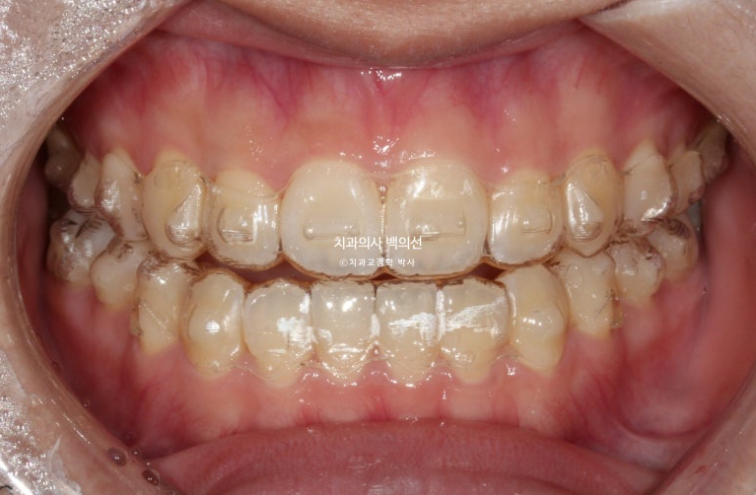

24.01

악궁확장장치 제거 후 인비절라인 장치제작에 들어갑니다.

인비절라인 장치를 기다리는 6주의 시간동안 악궁폭이 좁아지지 않도록 임시 유지장치를 만들어서

껴줍니다.

24년 2월부터 본격적으로 인비절라인 장치를 끼기 시작했습니다.